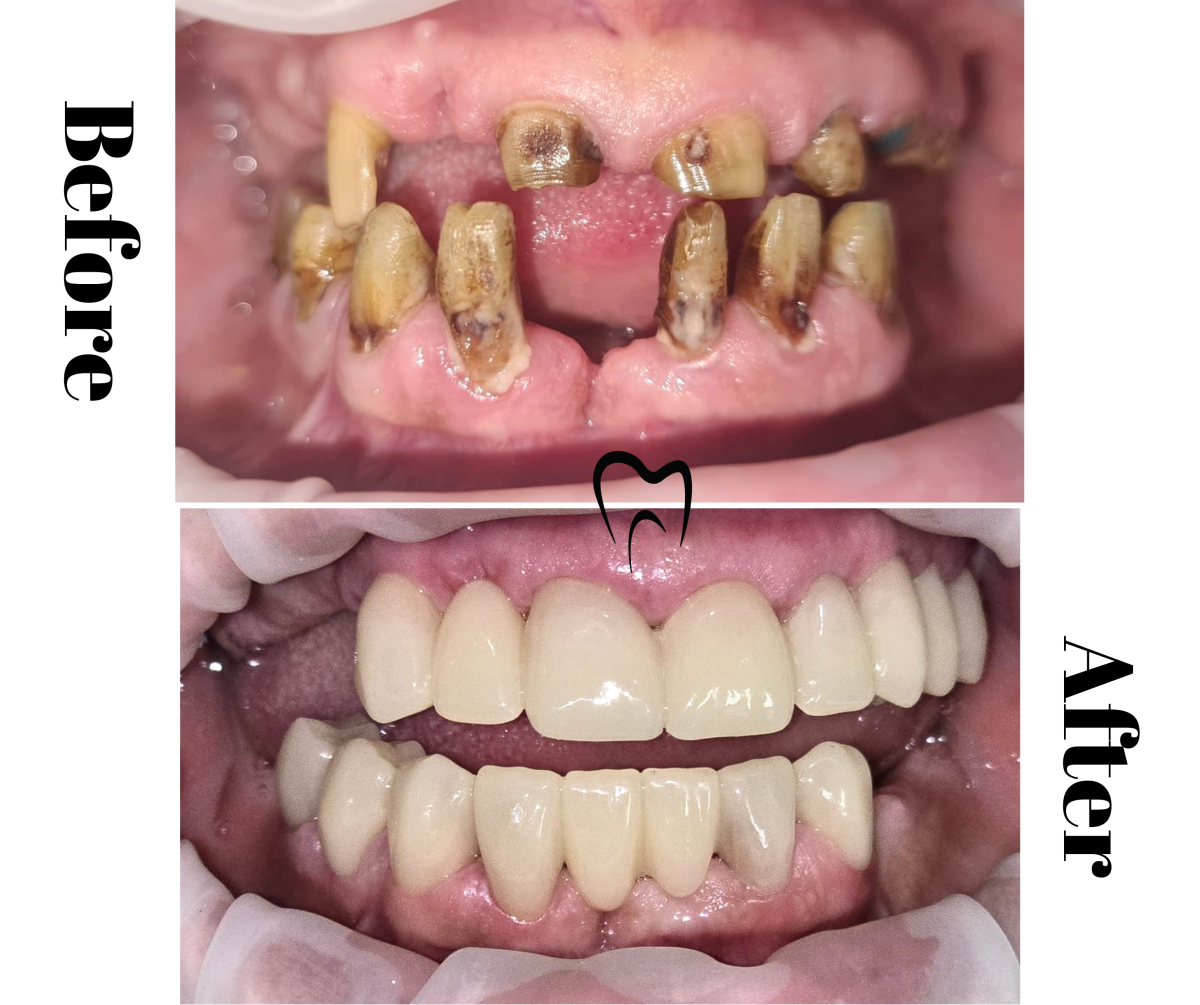

Lucrare superioară metalo-ceramică total fizionomică și proteză acrilică parțială inferioară

Lucrare metalo-ceramică total fizionomică